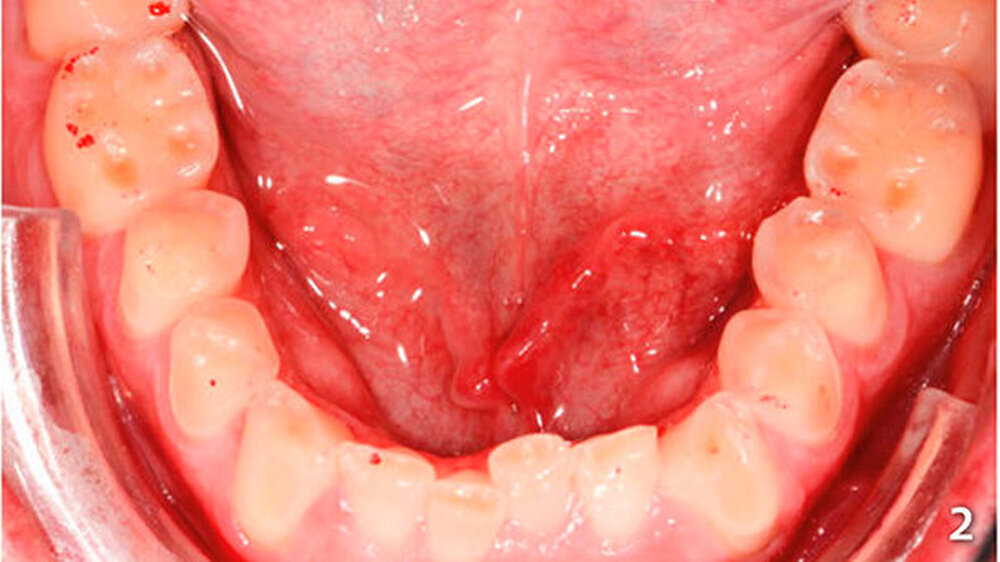

Der Patient wies an allen Frontzähnen sowie an den Seitenzähnen des Unterkiefers starke erosive Defekte auf (Abb. 1-3). Der Patient störte sich vor allem am Erscheinungsbild seiner Oberkieferfrontzähne und dem Engstand im Unterkiefer-Frontzahnbereich. Er wurde über verschiedene Therapiemöglichkeiten ausführlich aufgeklärt und entschied sich für direkte Rekonstruktionen mit Komposit. Im Februar 2016 erfolgte die Versorgung mit Kompositrestaurationen, wie folgt beschrieben.